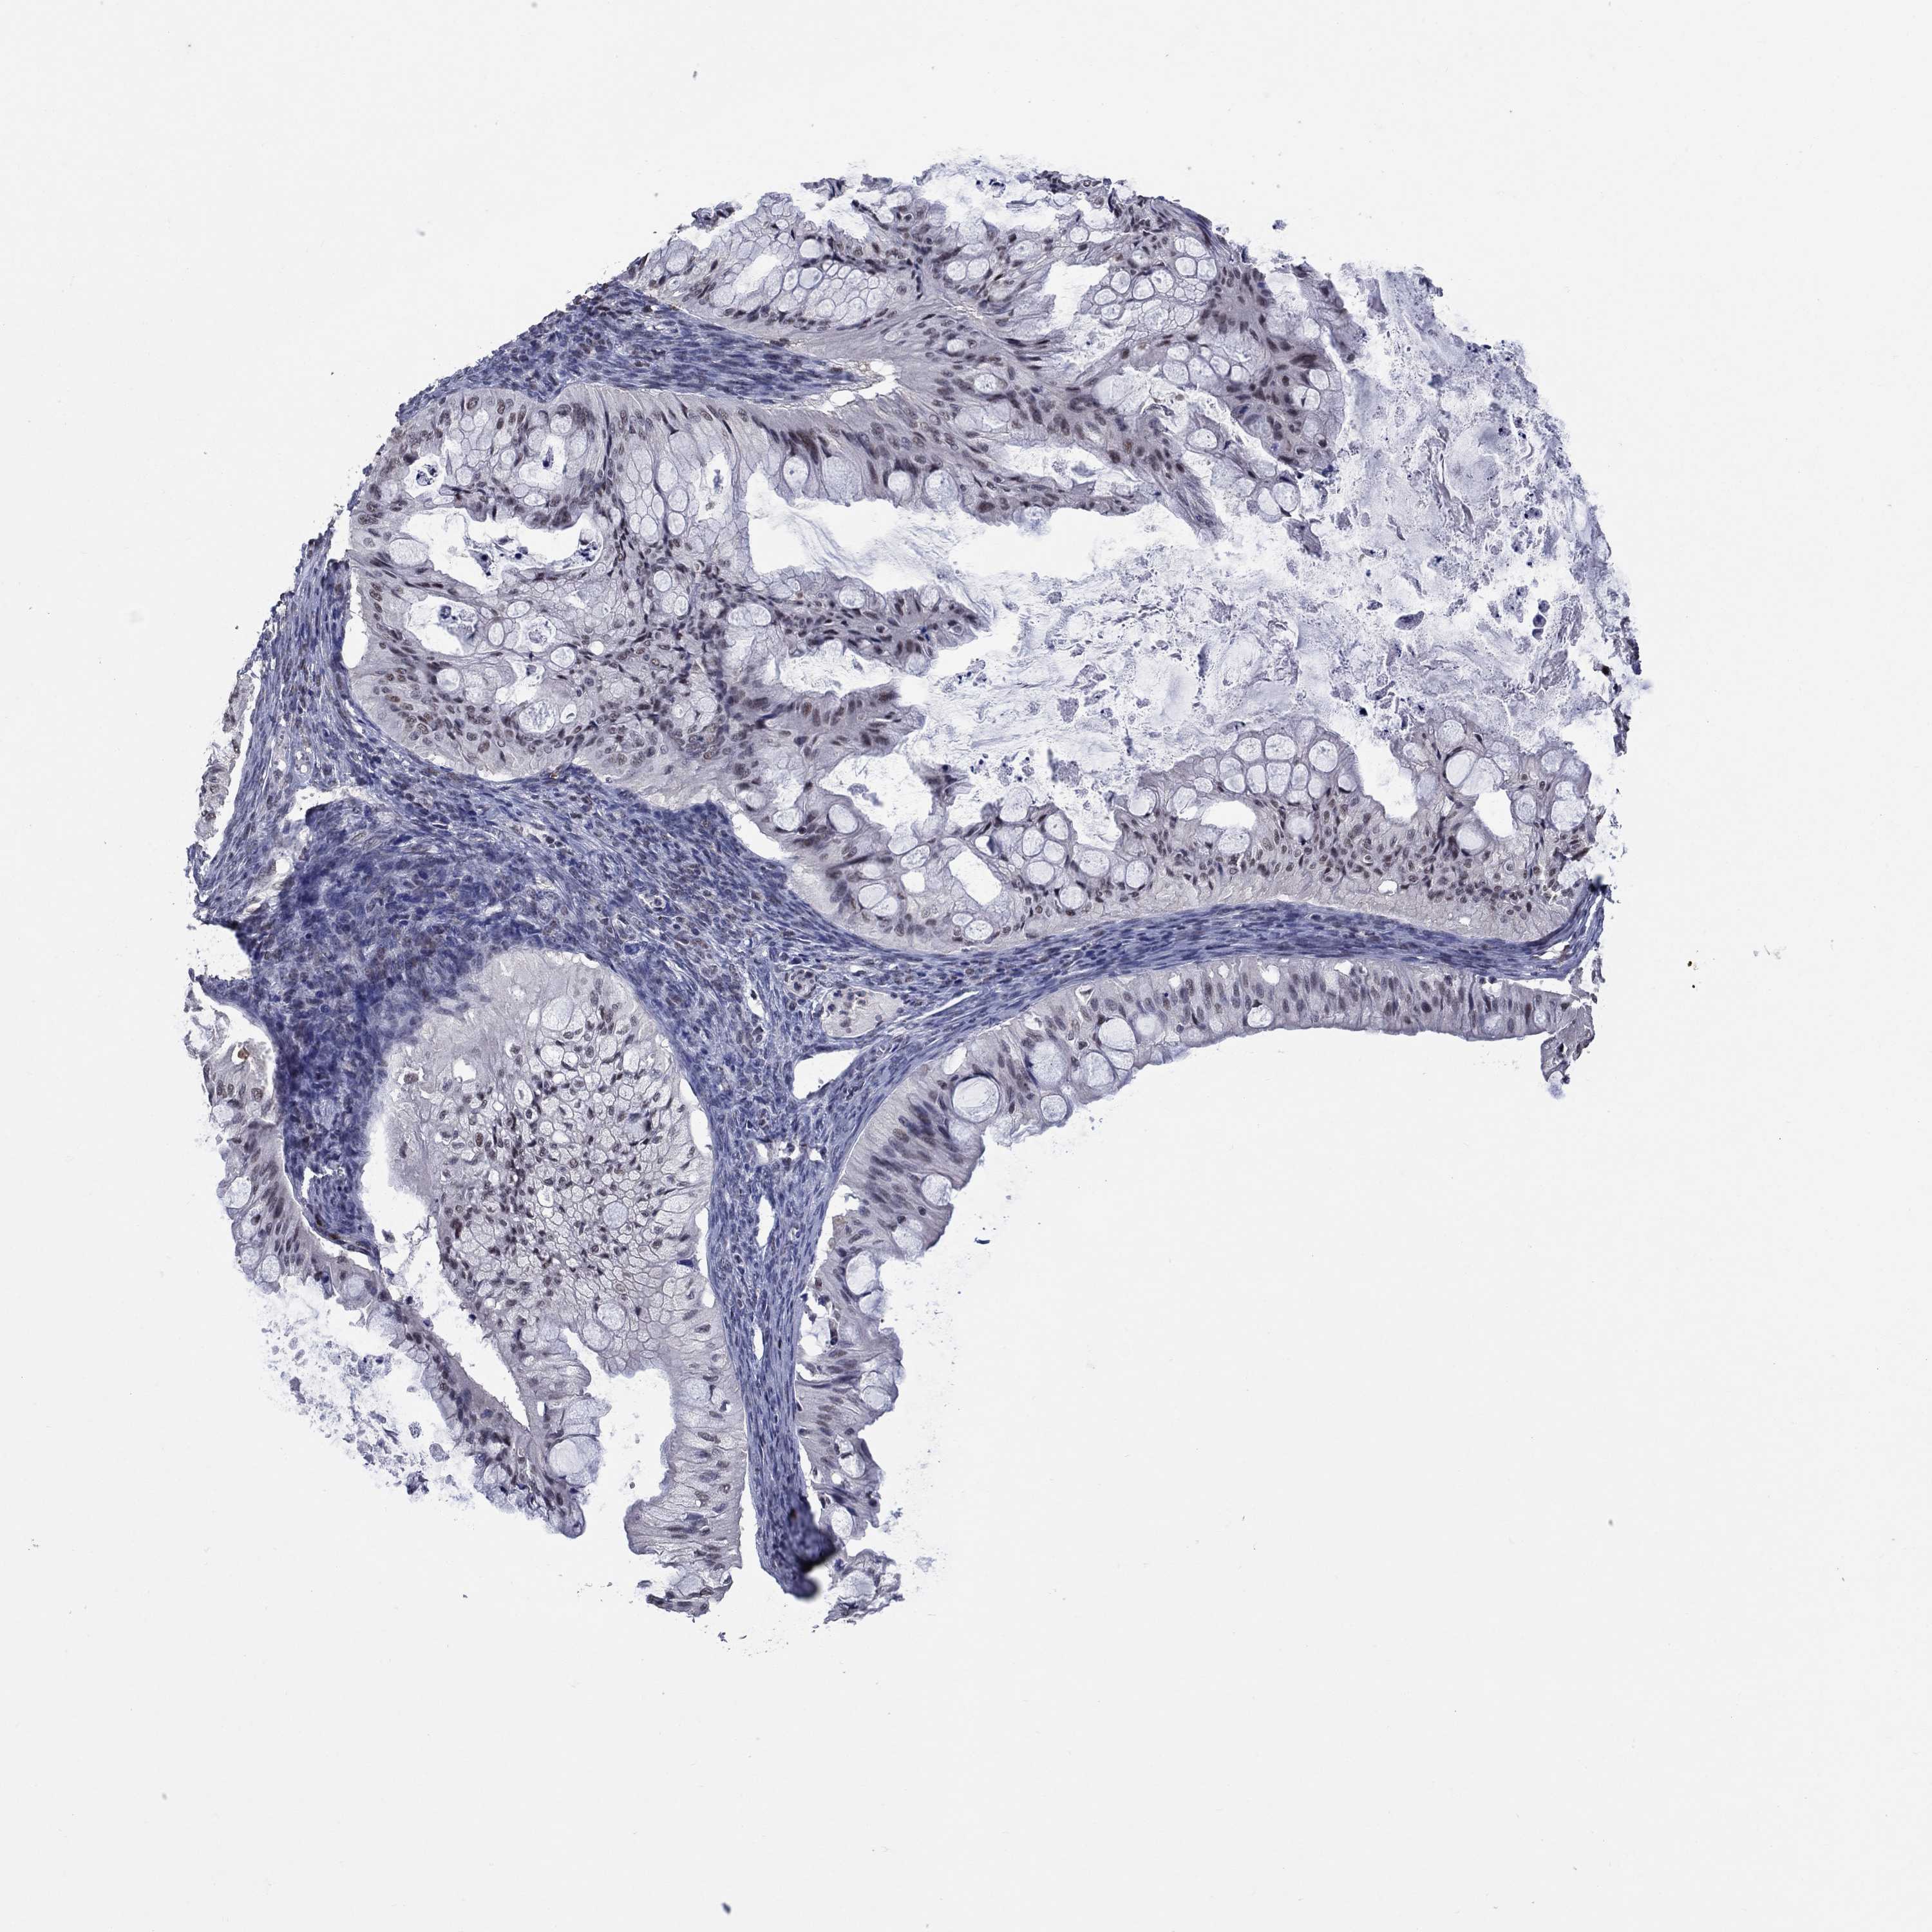

OVARIAN CANCER - Protein expressioni

A mouse-over function shows sample information and annotation data. Click on an image to view it in a full screen mode. Samples can be filtered based on level of antibody staining by selecting one or several of the following categories: high, medium, low and not detected. The assay and annotation is described here.

Note that samples used for immunohistochemistry by the Human Protein Atlas do not correspond to samples in the TCGA dataset.

Antibody stainingi

Antibody staining in the annotated cell types in the current human tissue is reported as not detected, low, medium, or high, based on conventional immunohistochemistry profiling in selected tissues. This score is based on the combination of the staining intensity and fraction of stained cells.

Each image is clickable and will lead to virtual microscopy that enables deeper exploration of all samples and also displays staining intensity scores, fraction scores and subcellular localization as well as patient and tissue information for each sample.

Antibody HPA074922

Antibody CAB002784

Cystadenocarcinoma, mucinous, NOS